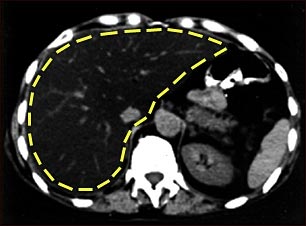

TC de grasa del hígado

Esta es una TC del abdomen superior que muestra un hígado graso (esteatosis del hígado). Se puede notar el agrandamiento del hígado y el color oscuro comparado con el bazo (cuerpo gris en el lado inferior derecho).